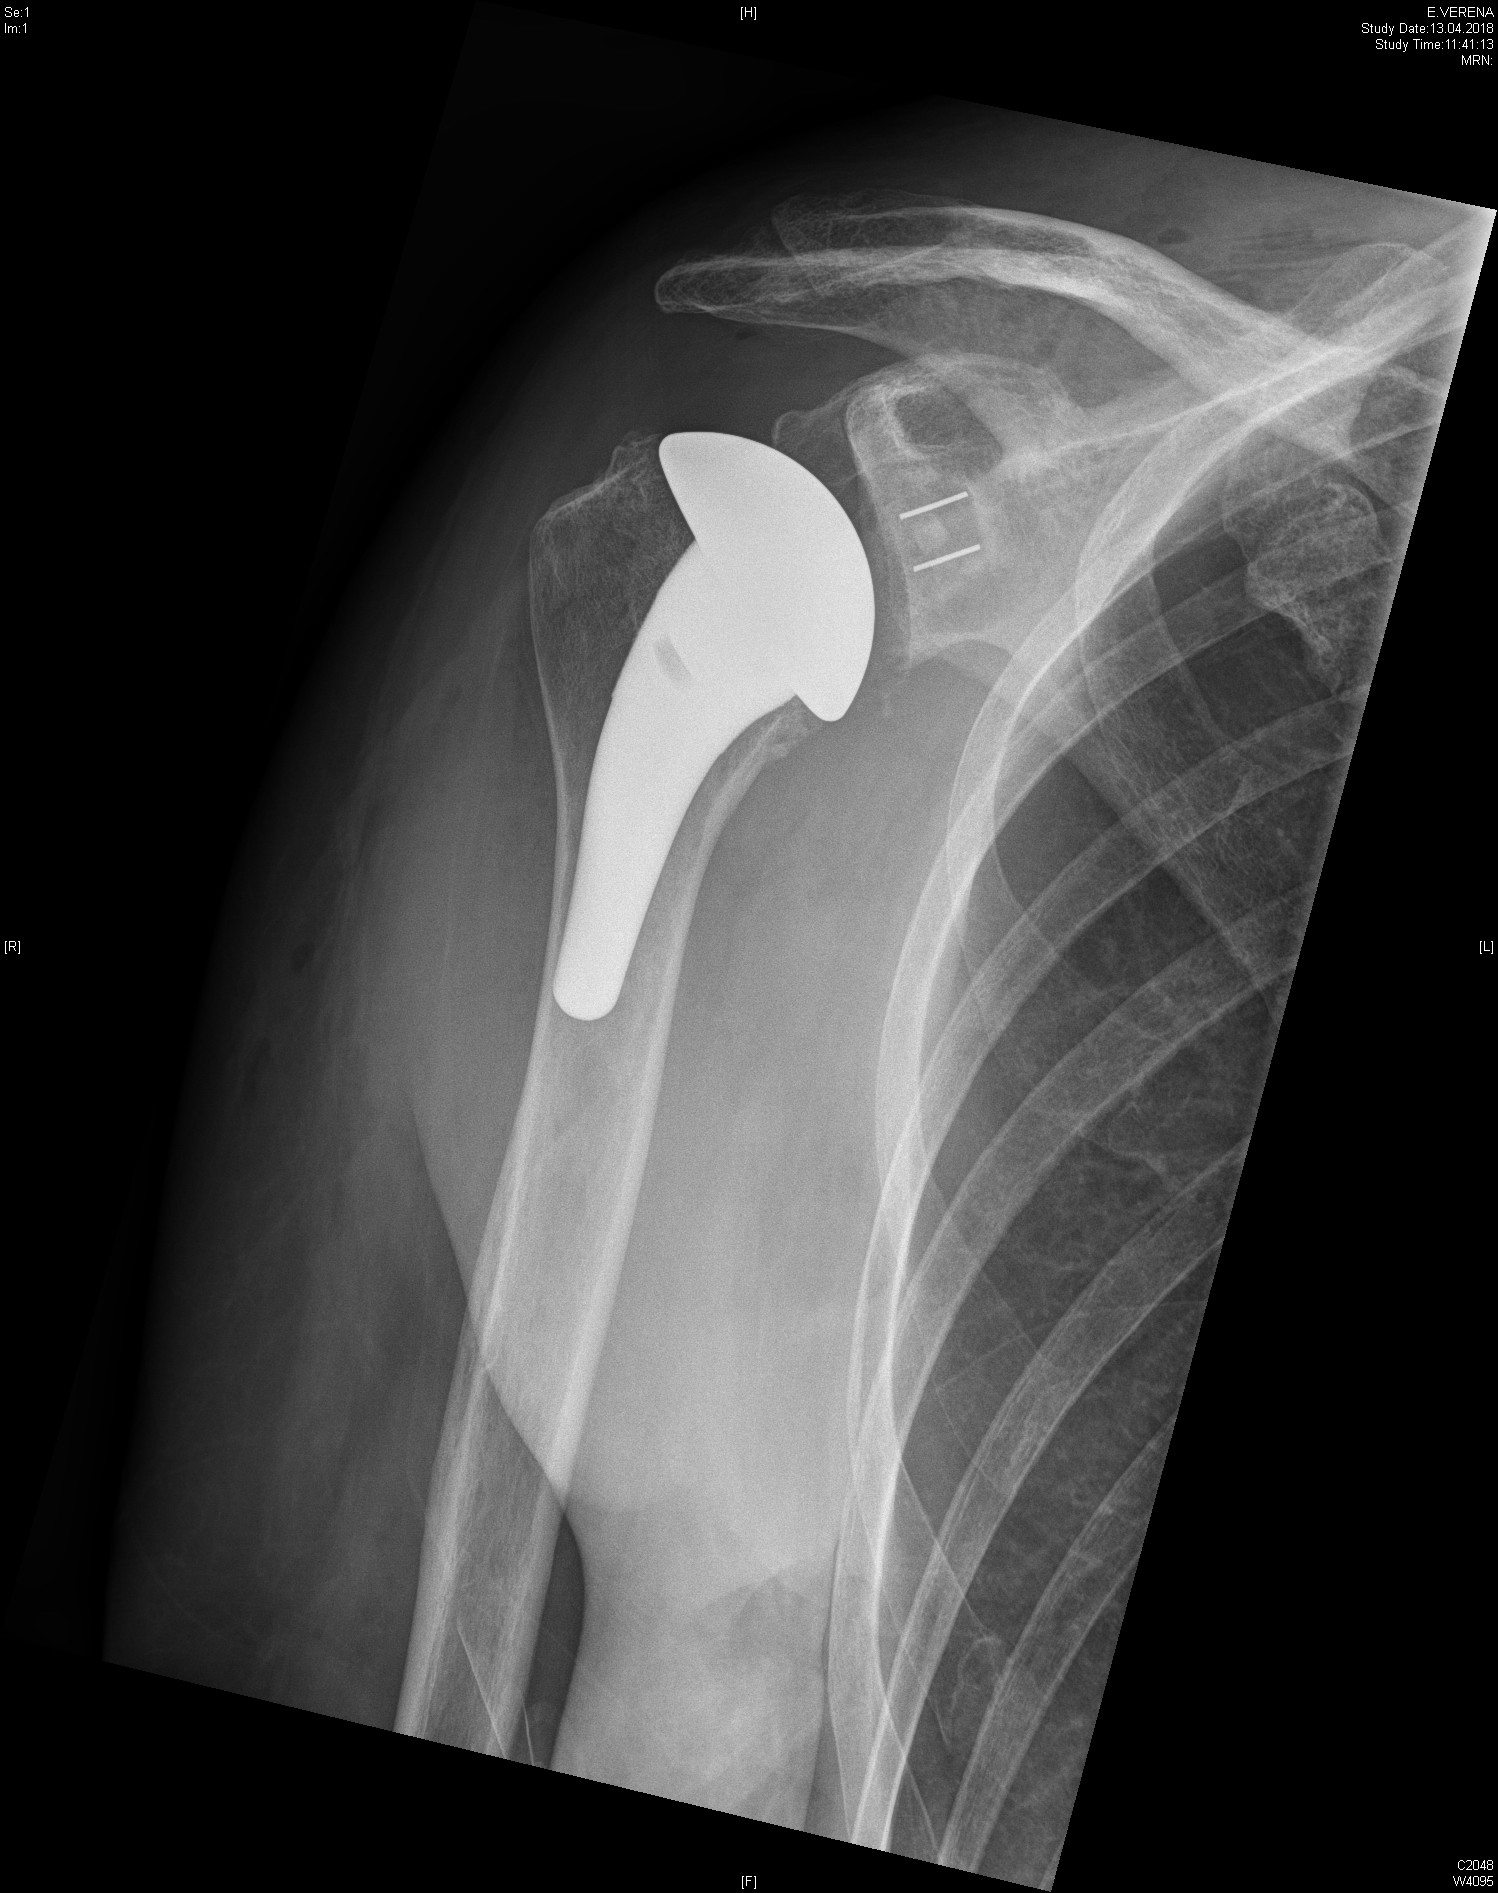

Depending on the individual situation, different types of prosthesis are used, such as the anatomical shoulder prosthesis or the inverse (reverse) prosthesis, which is particularly suitable for additional damage to the rotator cuff. In all cases, the focus is on precise diagnostics and individually tailored treatment planning.

Anatomical shoulder prosthesis